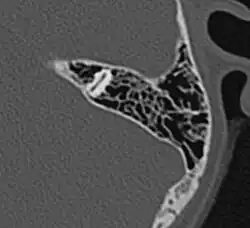

Die vom Mittelohr ausgehende Pneumatisation des Schläfenbeines ist mit dem fünften bis sechsten Lebensjahr weitgehend abgeschlossen. Ergebnis dieses Vorganges sind die pneumatischen Zellen, vor allem im Warzenfortsatz (Processus mastoideus). Es sind kleine, von Schleimhaut ausgekleidete Hohlräume, die durch unterschiedlich große Öffnungen miteinander und in der Gesamtheit mit dem Antrum mastoideum und damit mit dem Mittelohr in Verbindung stehen. Das Ausmaß der Pneumatisation des Schläfenbeines kann sehr unterschiedlich sein, es gibt Schläfenbeine mit fast komplett fehlender („gehemmter“) Pneumatisation, was meist als Folge häufiger Mittelohrentzündungen in der Kindheit anzusehen ist. Andererseits kann sich die Pneumatisation weit nach oben in die Schläfenbeinschuppe (Pars squamosa), nach vorne in den Jochbeinfortsatz (Processus zygomaticus) und in die Spitze der Felsenbeinpyramide ausdehnen. Es lassen sich im Warzenfortsatz typischerweise einzelne Zellgruppen oder Zellstraßen unterscheiden, die verschiedene Bezeichnungen tragen, wie Winkelzellen, Schwellenzellen, Terminalzellen usw. Dementsprechend werden bei ausgedehnter Pneumatisation Schuppenzellen (in der Schläfenbeinschuppe), Zygomaticuszellen (im Jochfortsatz), perilabyrinthäre Zellen (um das Labyrinth gelegen) und Pyramidenspitzenzellen unterschieden.